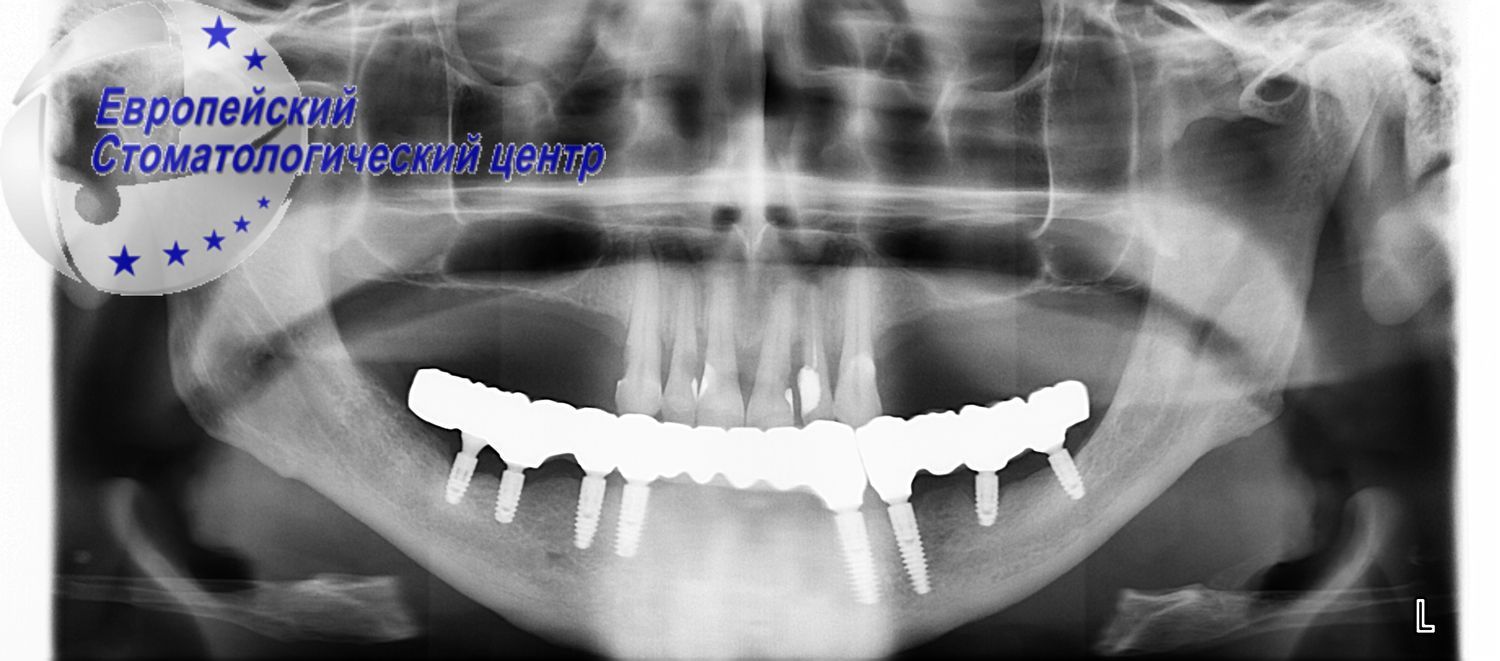

It was decided to remove the remaining teeth. The operation to install the implants was also complicated by the low quality and the height of the preserved bone. Nevertheless, the doctors at the European Dental Center managed to remove damaged teeth on the upper and lower jaws in one surgical procedure, disinfect the holes with an irbium laser, install 20 implants in a minimally invasive manner without additional incisions and complications, and establish a temporary non-removable structure every other day (see pic. 3-4).

Рicture 3

Picture 4

Currently, the patient expects full integration of implants and the installation of a permanent fixed structure. Fast (3 days) patient rehabilitation is achieved thanks to many years of experience, continuous improvement and equipment of doctors of the European Dental Center.